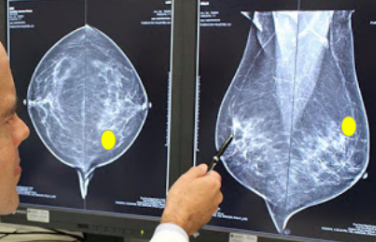

Dê a localização do tumor

Quadrante superior medial esquerdo